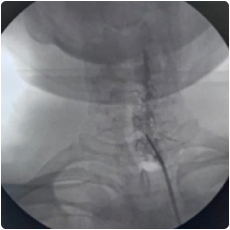

Cervical Facet injection is done under aseptic precautions in an operation theatre, under the guidance of fluoroscopy.

Intraop fluoroscopy image of needle placement at the cervical facet